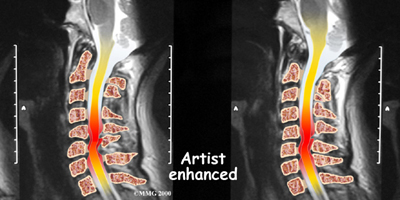

When the head and neck are suddenly and forcefully whipped forward and back, mechanical forces place excessive stress on the cervical spine. Traumatic disc rupture and soft tissue damage can occur. The cartilage between the disc and the vertebral bone is often cracked. This is known as a rim lesion.

Damage to the disc can put pressure on the nerves as they exit the spine. The pressure or irritation can be felt as numbness on the skin, weakness in the muscles, or pain along the path of the nerve. Most people think of these symptoms as indications of a pinched nerve. Health care providers call this condition cervical radiculopathy.

Magnetic resonance imaging (MRI)

If more information is needed, your doctor may order an MRI. The MRI machine uses magnetic waves rather than x-rays to create pictures of the cervical spine in slices. MRIs show the cervical spine vertebrae, as well as the soft tissue structures, such as the discs, joints, and nerves. MRI scans are painless and don't require needles or dye. MRI scan has become the most common test to look at the cervical spine after x-rays have been taken.